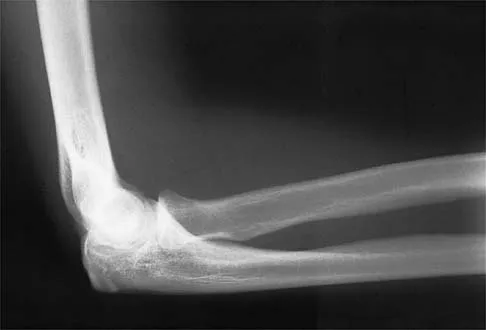

Figures 14a and 14b show the initial radiographs of an 18-year-old man who fell while snowboarding. Figures 14c and 14d show the radiographs obtained following closed reduction. Examination reveals that the elbow is stable with range of motion. Management should now consist of

Explanation

The initial radiographs reveal a simple elbow dislocation without associated fractures. After successful closed reduction, the range of stability should be assessed. If the elbow is stable, nonsurgical management should consist of a short period of immobilization followed by range-of-motion exercises. Immobilization for more than 3 weeks results in significant elbow stiffness. Surgical repair is indicated for dislocations that are irreducible, have associated fractures, or where stability cannot be maintained with closed treatment. Cohen MS, Hastings H II: Acute elbow dislocations: Evaluation and management. J Am Acad Orthop Surg 1998;6:15-23.